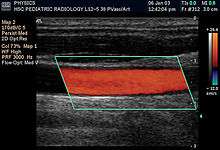

Doppler ultrasonography is used to study blood flow and muscle motion. The different detected speeds are represented in color for ease of interpretation, for example leaky heart valves: the leak shows up as a flash of unique color. Colors may alternatively be used to represent the amplitudes of the received echoes.

Sonography can be enhanced with Doppler measurements, which employ the Doppler effect to assess whether structures (usually blood)[16] are moving towards or away from the probe, and its relative velocity. By calculating the frequency shift of a particular sample volume, for example flow in an artery or a jet of blood flow over a heart valve, its speed and direction can be determined and visualised. This is particularly useful in cardiovascular studies (sonography of the vascular system and heart) and essential in many areas such as determining reverse blood flow in the liver vasculature in portal hypertension. The Doppler information is displayed graphically using spectral Doppler, or as an image using color Doppler (directional Doppler) or power Doppler (non directional Doppler). This Doppler shift falls in the audible range and is often presented audibly using stereo speakers: this produces a very distinctive, although synthetic, pulsating sound.

It should be noted here that there are no standards for the display of color Doppler. Some laboratories show arteries as red and veins as blue, as medical illustrators usually show them, even though some vessels may have portions flowing towards and portions flowing away from the transducer. This results in the illogical appearance of a vessel being partly a vein and partly an artery. Other laboratories use red to indicate flow toward the transducer and blue away from the transducer. Still other laboratories prefer to display the sonographic Doppler color map more in accord with the prior published physics with the red shift representing longer waves of echoes (scattered) from blood flowing away from the transducer; and with blue representing the shorter waves of echoes reflecting from blood flowing toward the transducer. Because of this confusion and lack of standards in the various laboratories, the sonographer must understand the underlying acoustic physics of color Doppler and the physiology of normal and abnormal blood flow in the human body (see Red shift[17][18][19]).